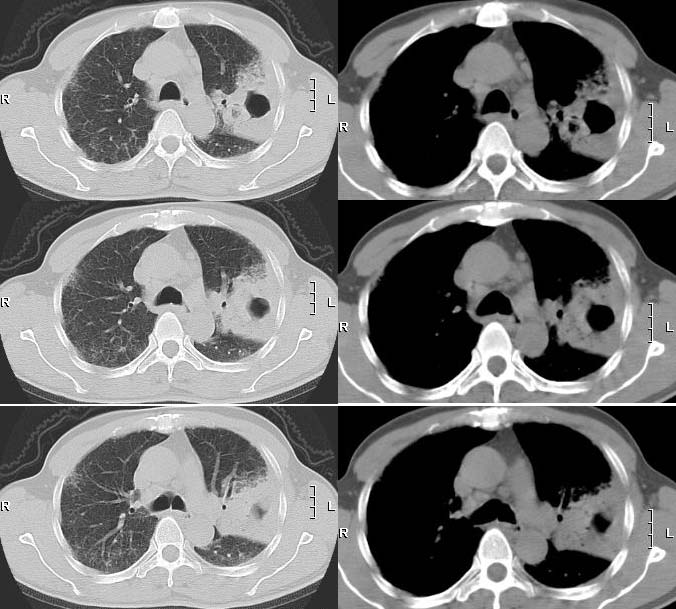

标题: 回复:建议;站内肺部球型阴影讨论

再来个空洞性肺癌,男,58岁,有咳嗽,咳痰,咯血,我看到片子时已经是治疗后复查了,第一次片子,空洞里充满了积液。

[本贴已被 jiajie 于 2006-3-8 19:19:06 修改过]